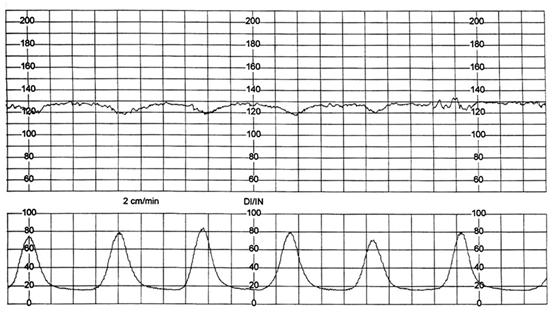

Fig. nr. 313. Pacienta M.M. - hiperkinezie la dilatatia de 5 cm, nastere pe cale vaginala, nou-nascut prematur, 2350 gr., Apgar 8/1' ( 1 cm / min )

Fig. nr. 314. Pacienta C.A., hiperkinezie uterina, nastere pe cale vaginala, nou-nascut 3600 gr, Apgar 9/1' (1 cm / min)

Fig.nr.315. Pacienta A.G. - hiperkinezie la dilatatia de 3 cm, nastere pe cale vagi-nala, nou-nascut de 3600 gr., Apgar 10/1', pH din cordonul ombilical 7,209 (1 cm / min)

Fig. nr. . Pacienta U.M. - hiperkinezie la dilatatie de 4 cm, nastere pe cale vaginala, nou-nascut de 2900 gr., Apgar 9/1', pH din cordonul ombilical 7,209.( 1 cm / min)

Fig. nr. 3 Pacienta S.B. - sindrom de hiperstimulare (hiperkinezie si deceleratii variabile prelungite ale ritmului cardiac fetal) la 4 cm dilatatie - operatie cezariana , nou nascut postmatur, 3750 gr., Apgar 9/1' si 10/5' (1 cm / min)